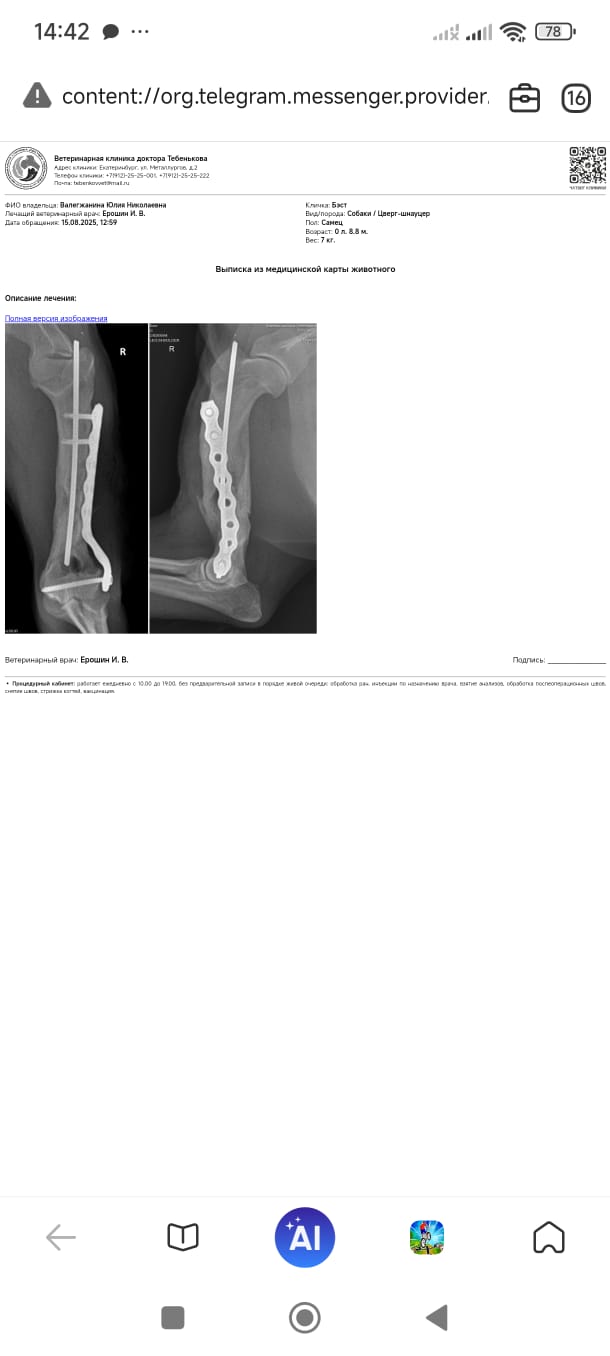

Лиза отвезла зверя к ортопеду на ещё одну консультацию.

Он сказал, что перелом несвежий, недели 2.

Сегодня оставили на операцию, поставят пластину, а завтра домой. Еще я попросила лишние зубы заодно вынуть.

Операцию сделали, завтра утром выдадут обратно.

Лапу надо беречь, прыжки исключать, поверхности не скользкие, нагрузки избегать.

Через 10 дней снимать швы, через полтора месяца контроль.

Доктор сказал, что такие старые оскольчатые переломы плохо срастаются.

Бэста выдали из клиники, операцию сделали, швы снимать через 10-12 дней и контрольный рентген через полтора месяца.

Выписка в регистратуре, все идет по плану, через 6 недель контрольный рентген.

2. Бэсту потихоньку снимают винты с лапы.